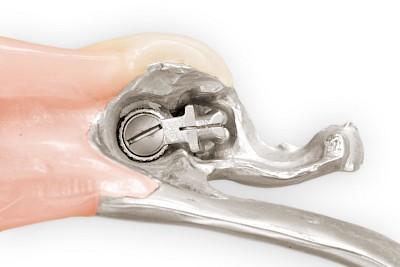

Manchmal sind Zahnprothesen auch über komplizierte Verankerungselemente (Riegel) mit den Restzähnen verbunden. Zudem werden nicht selten die verschiedenen Verbindungselemente kombiniert. Teilprothesen sind sehr vielfältig und zum Teil technisch sehr aufwendig gefertigt. Deshalb ist auch die Handhabung (Einsetzen, Herausnehmen, Reinigen) nicht immer einfach und selbsterklärend. Wenn immer möglich, sollte der betroffene Mensch selbst seine Prothesen entnehmen und einsetzen – meist haben diese jahrelange Übung und kennen die "Tricks"

Beispiele mit Riegelelementen bzw. Monoreduktoren 48 Bilder

Abzugshilfen

Das Herausnehmen von Zahnprothesen ist mitunter schwierig. Grundsätzlich können leichte Rüttelbewegungen das Herausnehmen erleichtern. Die Prothese sollten immer gut – am besten auf beiden Seiten gleichzeitig – mit Daumen und Zeigefinger gehalten werden, damit die Prothese nicht unbeabsichtigt aus den Fingern nach hinten in den Rachen fällt. Bei Klammerprothesen sollte direkt an den Klammern von unten angesetzt und gleichzeitig von oben gegengehalten werden. Bei Riegelprothesen müssen zunächst die Riegel (in der Regel gibt es zwei Riegel – einen auf der linken und einen auf der rechten Seite) geöffnet werden. Wenn sich die Prothese festhakt, ist es am besten, die Prothese einfach wieder zurückzudrücken und erneut einen Versuch zu starten.

Manchmal werden an den Prothesen auch spezielle Abzugshilfen eingearbeitet. Kompressen als Hilfsmittel können geeignet sein und schließlich gibt es auch im Handel sogenannte Prothesenabzieher.

Klemmt eine Prothese oder bestehen Unsicherheiten beim Herausnehmen, sollte ein Zahnarzt gerufen werden.

Beispiele 21 Bilder